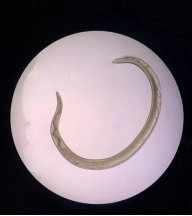

這些蟲子在眼睛里是游動狀態(tài),十分靈活,一碰就游走,每條長約1厘米到2厘米不等,跟縫衣線一樣粗細!

經(jīng)醫(yī)院檢驗科化驗得知,這種蟲子是一種寄生蟲,叫做結(jié)膜吸吮線蟲。為什么寄生蟲會跑進豆豆的眼睛里?

結(jié)膜吸吮線蟲,蟲體細長、半透明、淡紅色,離開宿主之后變成乳白色。